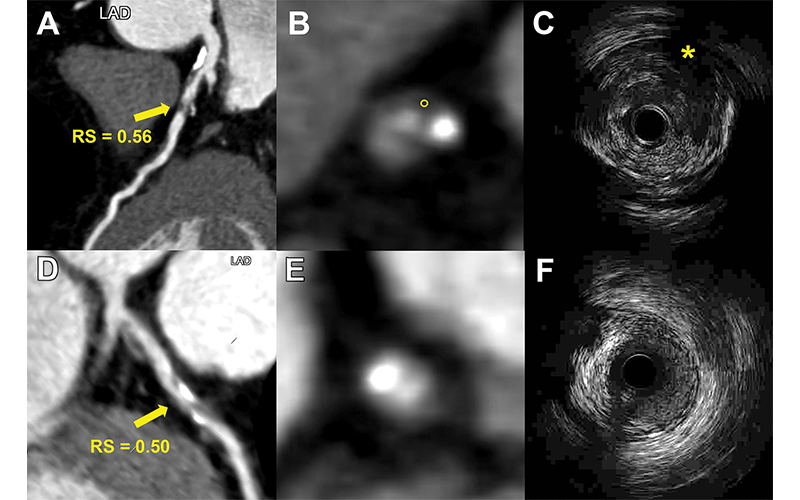

Representative images from two patients demonstrate the use of a radiomic signature (RS) to discriminate vulnerable plaques defined with intravascular US. (A–C) Images depict a vulnerable plaque with a high RS. (A) Image from coronary CT angiography (CCTA) shows a partially calcified plaque (arrow) with RS value of 0.56 in the proximal left anterior descending artery (LAD). (B) Corresponding axial CCTA image shows the plaque with low-attenuation area (circle, 25 HU). (C) Corresponding intravascular US scan confirms the plaque as an attenuated plaque (*). (D–F) Images show a nonvulnerable plaque with low RS. (D, E) CCTA images show a partially calcified plaque (arrow in D) with RS value of 0.50 in the proximal left anterior descending artery. (F) Corresponding intravascular US scan confirms the plaque as a partially calcified plaque without echo attenuation and echolucent zone. High versus low RS lesion was defined using an optimal cut-off value of 0.53 (range, 0.46–0.58).

The model enabled the detection of vulnerable plaques associated with an increased risk for major adverse cardiac events like heart attacks. A high radiomic signature was independently associated with these events over a median three-year follow-up.